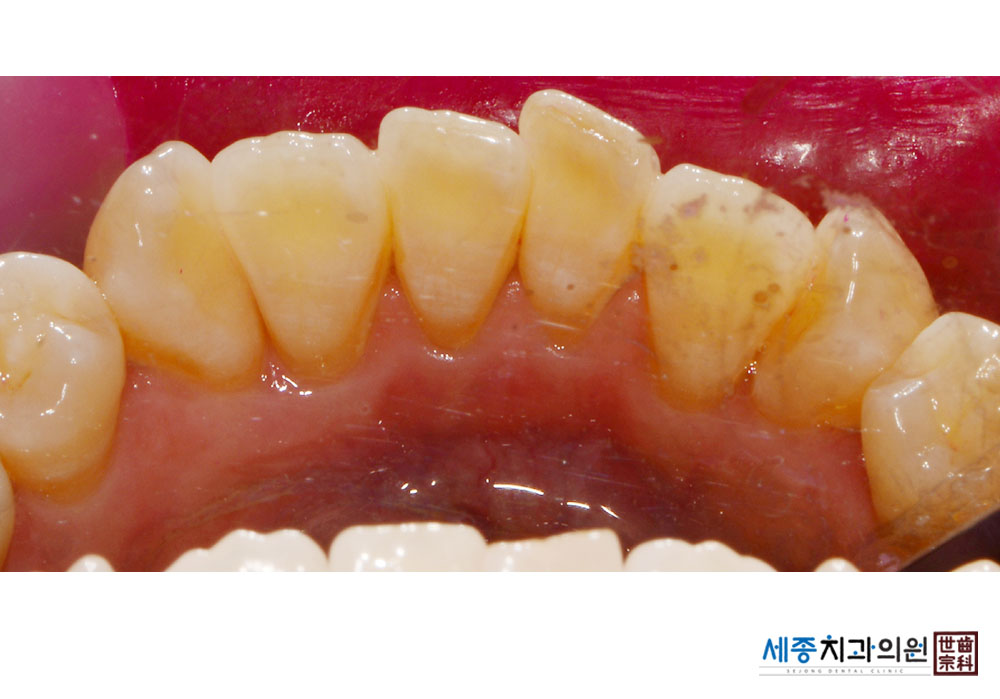

[스케일링] 치주질환 예방 스케일링

치료전 : 2023-12-21

가글마취&저주파 스켈러를 사용한 착색제거 스케일링